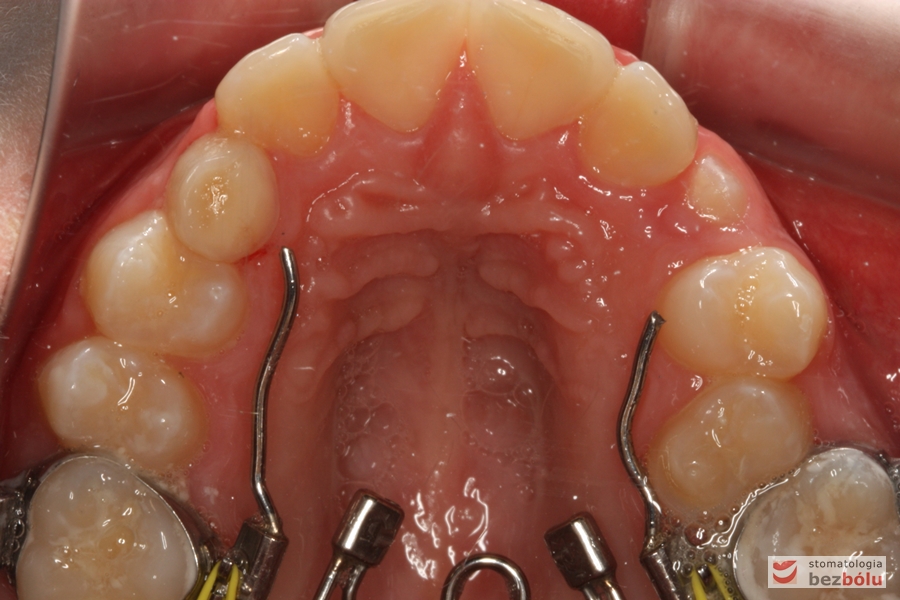

Rodzice zgłosili się z pacjentem celem rutynowej kontroli ortodontycznej. Wykonano OPG i po analizie modeli diagnostycznych stwierdzono brak miejsca dla wyrzynania dolnej prawej piątki stałej oraz zwężenie szczęki wraz z rotacją górnych zębów szóstych. W łuku górnym w pierwszym etapie leczenia zastosowano Rotator, celem odrotowania 6-tek stałych oraz ekspansji łuku w wymiarze poprzecznym. Następnie zamontowano aparat stały metalowy do uszeregowania zębów w łuku. W łuku dolnym miejsce odtwarzano stosując aparat stały i odpowiednią mechanikę leczenia. Leczenie aktywne trwało 3,5 roku, po czym zastosowano terapię retencyjną (retainer stały w żuchwie oraz Płytkę Hawley’a w szczęce).